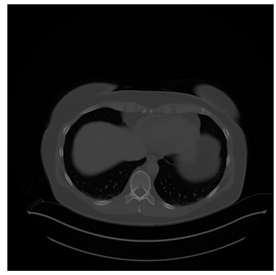

4.3. The Results

In this subsection, we describe three experiments used to measure the performance of the proposed method. The first experiment shows the stegoimage and marks the pixels’ positions that have been modified during the embedding process, as shown in Table 2, Table 3, Table 4, Table 5, Table 6 and Table 7. To make modified pixel positions have a pronounced effect, we set bpp (bit per pixel) rate at 0.05 and 0.025. It can be seen from the results that the proposed local complexity function can distinguish ROI and RONI from most of the medical images, so modified pixels are mainly gathered in RONI. However, it is observed that the proposed local complexity function cannot distinguish between ROI and RONI in the Prostate-MRI database due to the relative complexity of the image. Besides, “Modified BPP” represents the proportion of pixels in the image that have been modified. We observed that the performance of “baboon” in the grayscale standard images database is poor because that image’s pixels are relatively complex. It becomes challenging to select the more embeddable pixels based on the proposed local complexity function. Nevertheless, the modified pixel positions in other grayscale standard images, such as Lena and Barbara, are relatively smooth, verifying that our local complexity function is also applicable to general images.